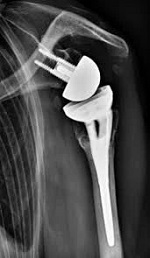

2022年底,史賽克(Stryker,紐交所代碼:SYK)宣布,旗下Tornier Pyrocarbon熱解碳肱骨頭通過美國食品藥品監(jiān)督管理局(FDA)的De Novo分類通道審批,允許進(jìn)入美國市場銷售。

據(jù)公開新聞顯示,Armodios M. Hatzidakis博士與FAAOS、西部骨科公司、丹佛手術(shù)中心、羅斯醫(yī)學(xué)中心通力合作完成美國第一例使用Tornier Pyrocarbon肱骨頭的肩關(guān)節(jié)置換手術(shù)。

Pyrocarbon是一種高性能生物材料,廣泛應(yīng)用于骨科和手部外科手術(shù)。這種材料的主要優(yōu)點(diǎn)是其生物相容性和耐磨性。Pyrocarbon在生物力學(xué)方面與人體天然軟骨相似,因此可以更好地適應(yīng)人體的生理環(huán)境。此外,它還具有優(yōu)越的耐磨性能,使得植入物在關(guān)節(jié)運(yùn)動時磨損更少。在美國,史賽克是第一家經(jīng)FDA批準(zhǔn)銷售Pyrocarbon肩部半關(guān)節(jié)植入物的公司。